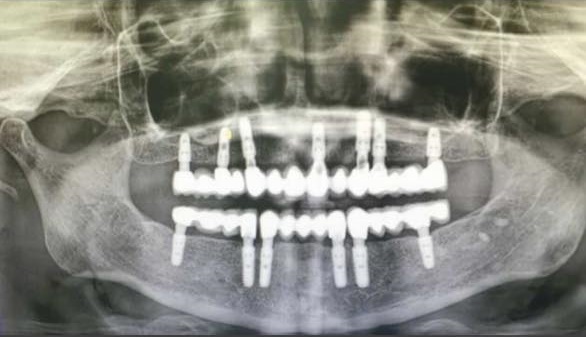

İmplant Diş Nasıl Yapılır ?